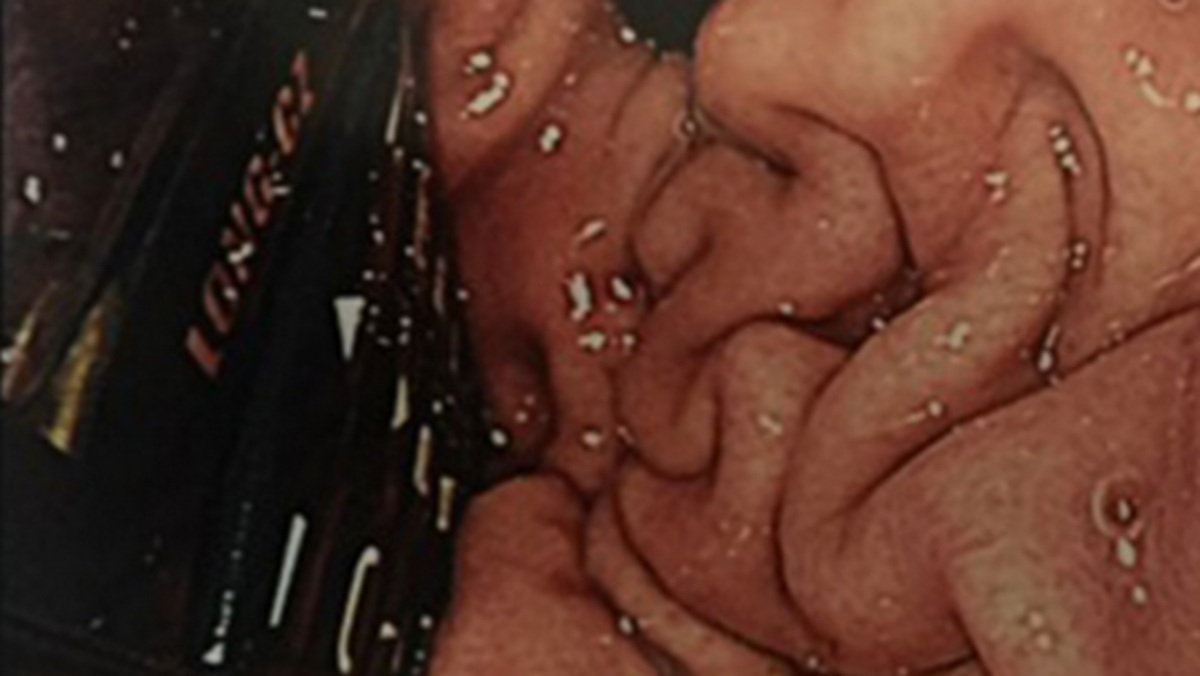

وحاول المسعفون في بداية الأمر إخراج الهاتف عبر إدخال منظار طبي إلى جوف السجين، لكن هذه المحاولة أخفقت.

وأشاروا إلى أن الأمر يتطلب إجراء عملية شق البطن وإخراج الهاتف الذي استقر في المعدة، واستطاعوا في نهاية المطاف إخراج الهاتف من خلالها.